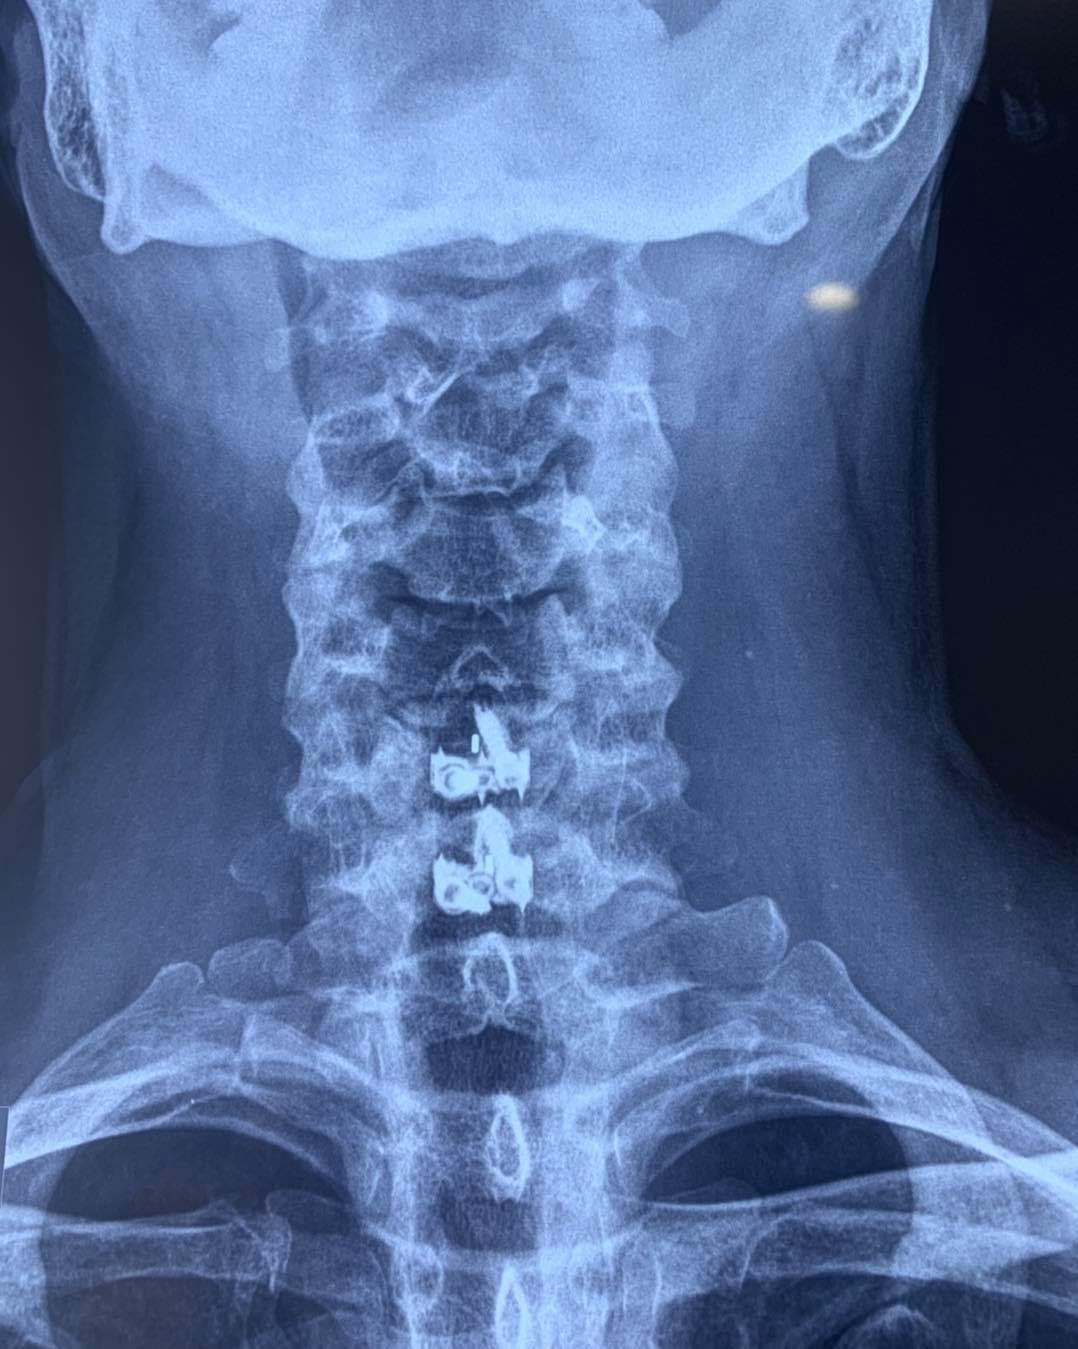

CIRUGIAS

RESULTADOS